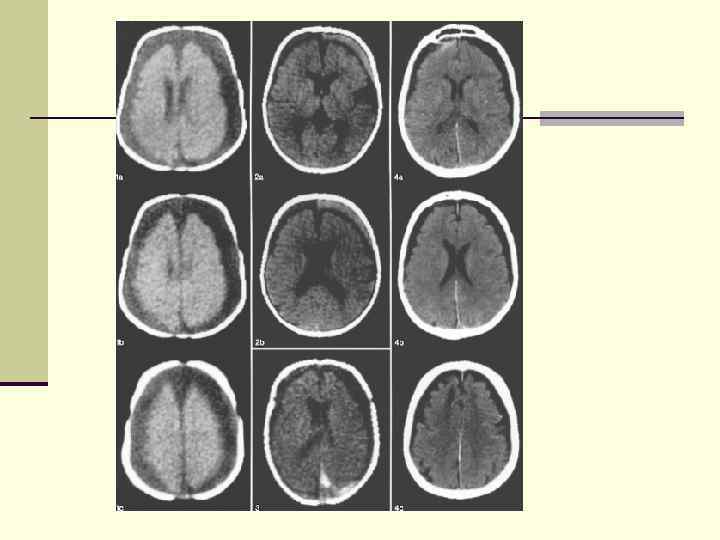

Хронические субдуральные гематомы. Варианты плотности а) гиподенсивная б) гиперденсивная в) изоденсивная г) гетероденсивная Хронические субдуральные гематомы. Варианты плотности а) гиподенсивная б) гиперденсивная в) изоденсивная г) гетероденсивная

Хронические субдуральные гематомы Хронические субдуральные гематомы